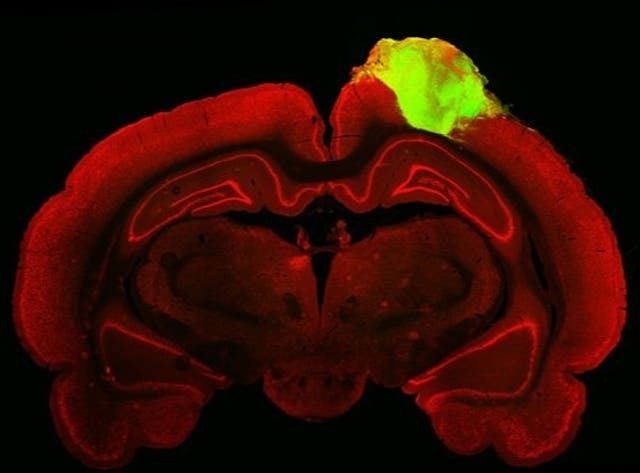

Чтобы проверить, насколько хорошо органоид интегрирован с мозгом крысы, исследователи ввели вирусы с флуоресцентными метками в глаз крысы, чтобы увидеть, по какому пути синапса он следует. Флуоресцентный материал прошел весь путь от сетчатки до недавно пересаженного органоида, предполагая полную функциональную интеграцию.

Затем зрение крысы было проверено с помощью мигающих огней и изображений, и ученые заметили, что около четверти пересаженных человеческих нейронов отреагировали на симуляцию.

“Мы увидели, что большое количество нейронов внутри органоида реагировало на определенную ориентацию света, что дает нам доказательства того, что эти органоидные нейроны были способны не просто интегрироваться со зрительной системой, но и перенять очень специфические функции зрительной коры”, - сказал доцент Чен.